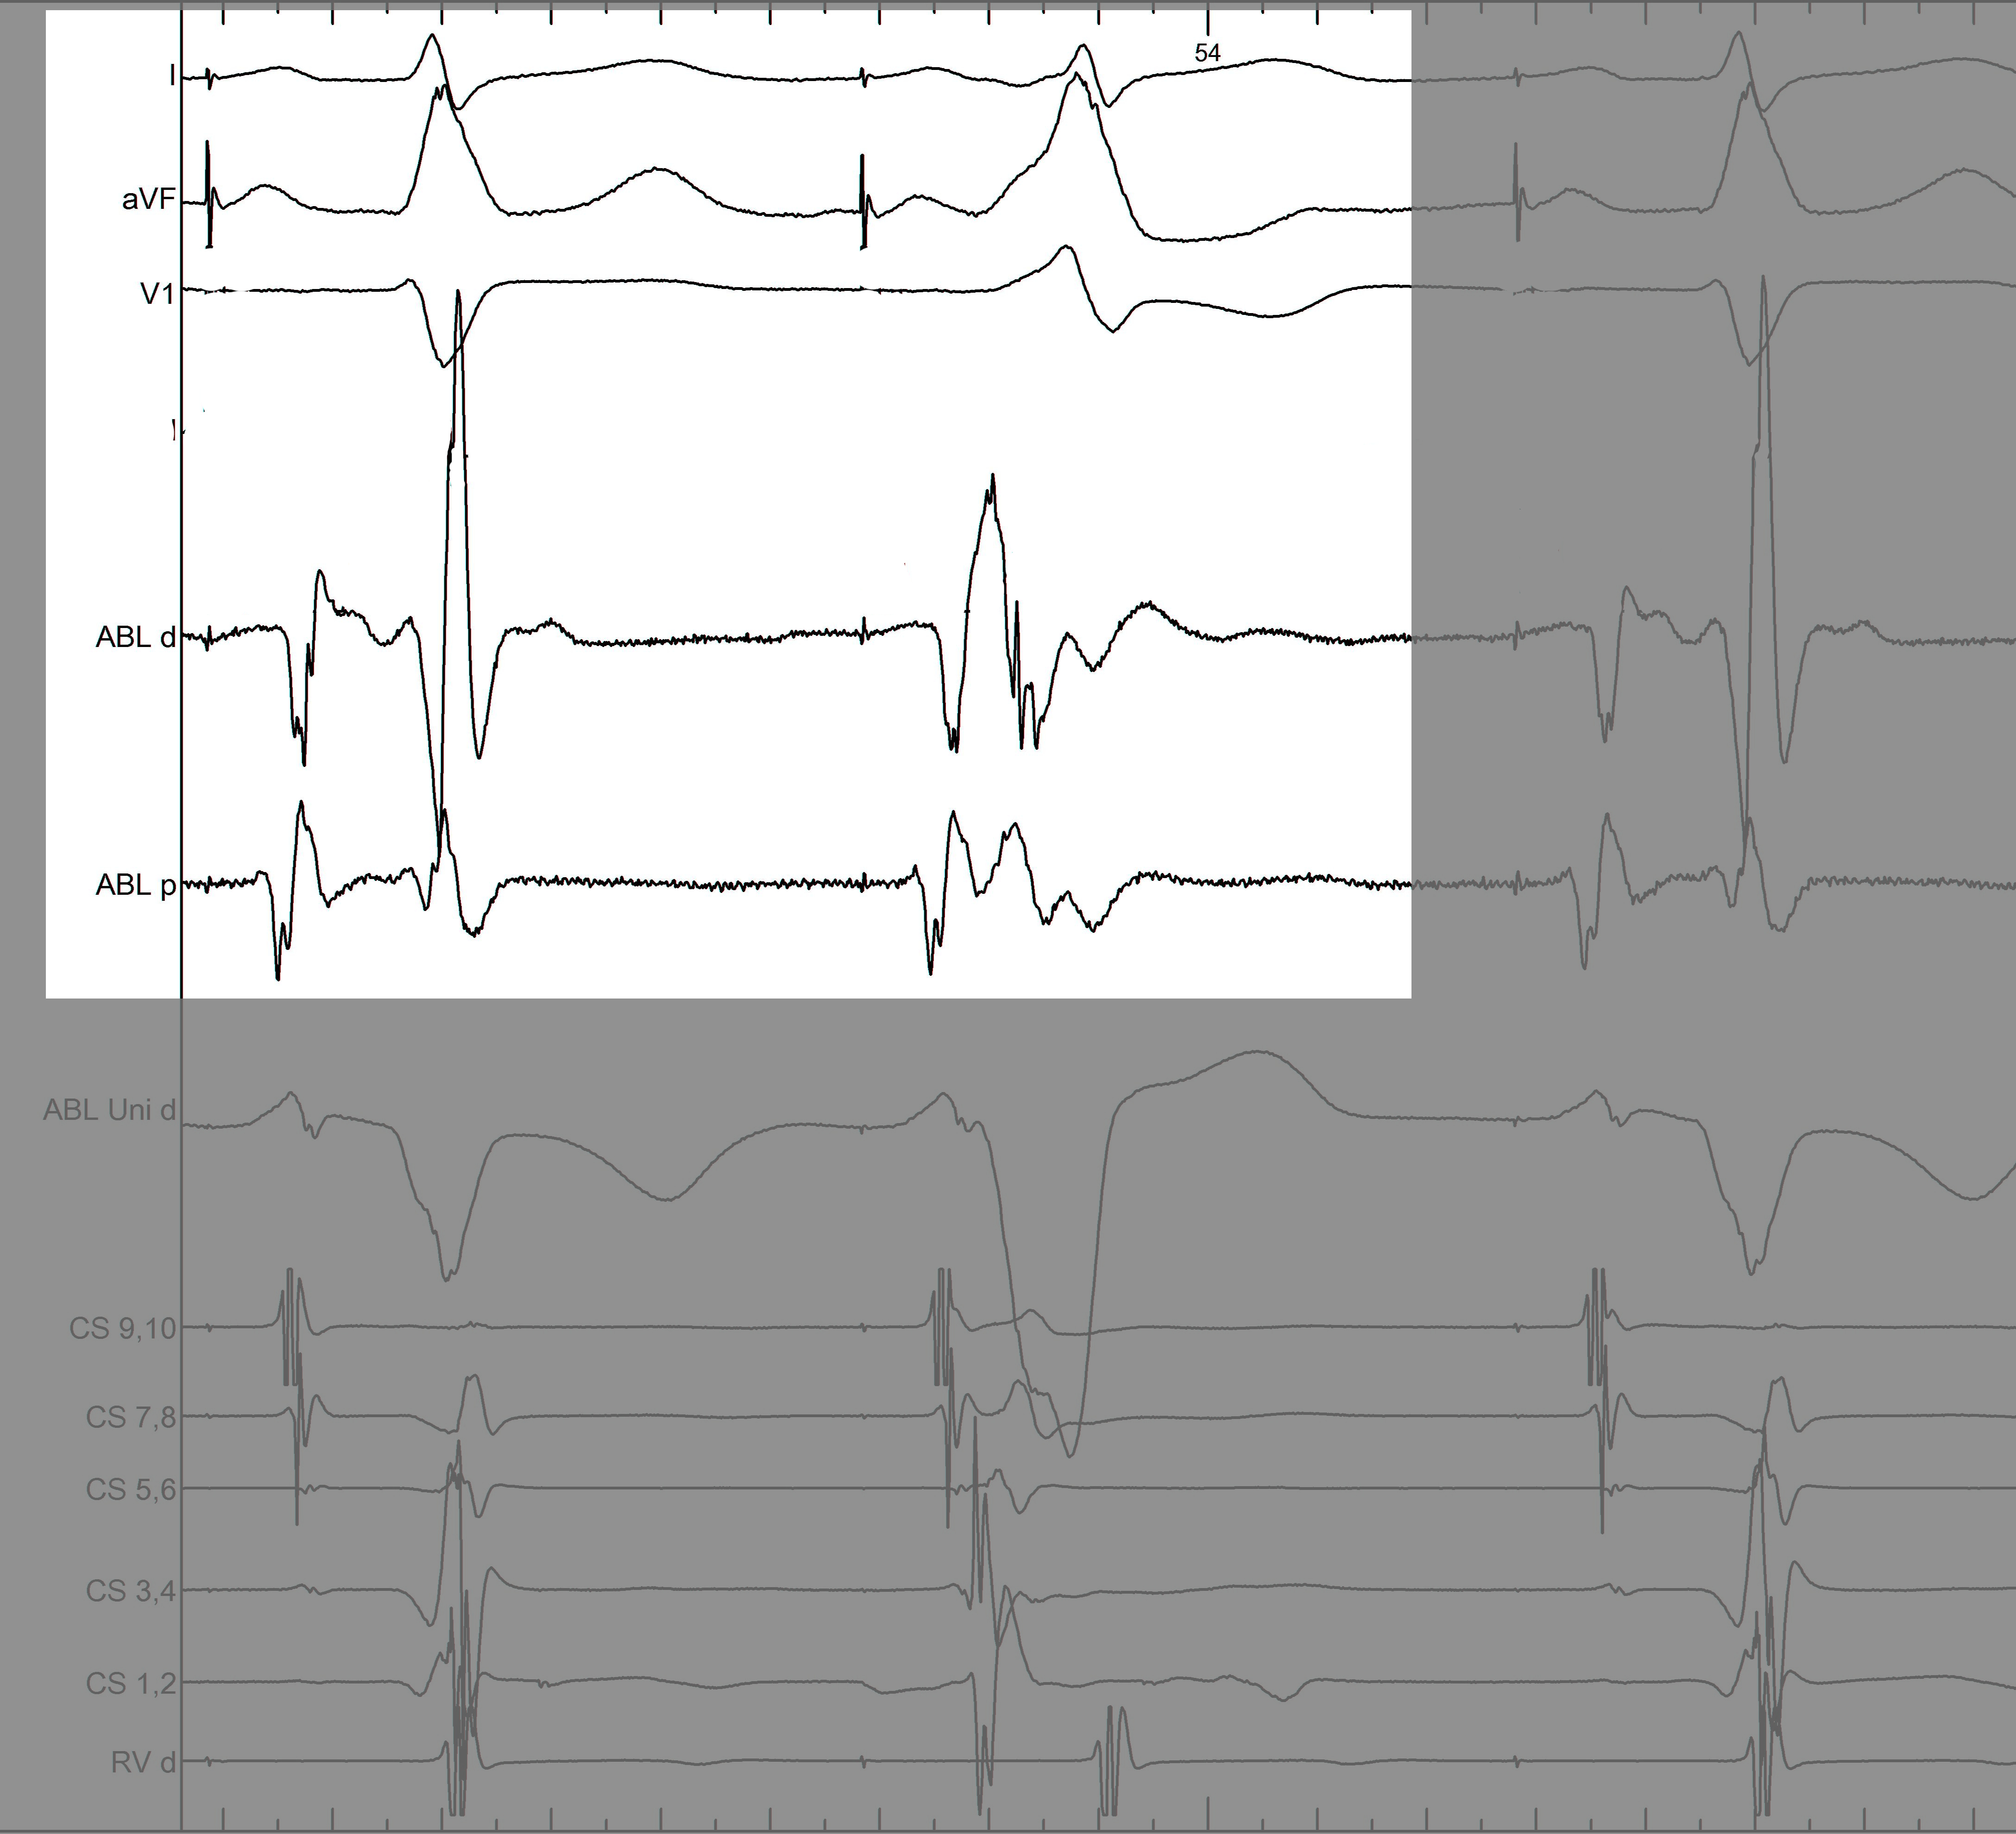

mask1.jpg

Information from other electrodes

mask2.jpg

Unipolar

mask3.jpg

Non preexcited beats

mask4.jpg